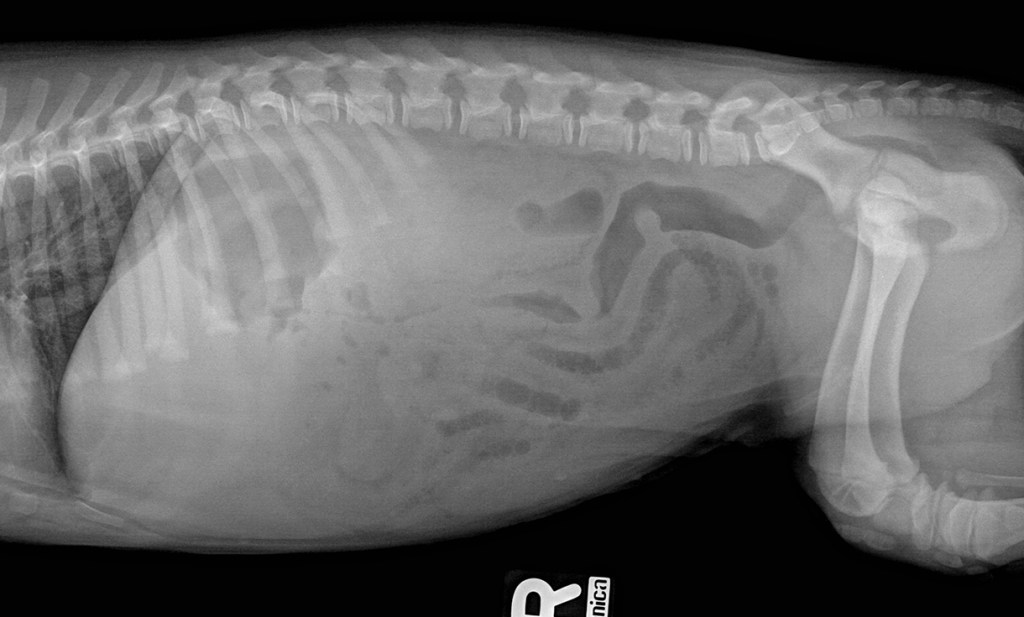

latD_1220pix